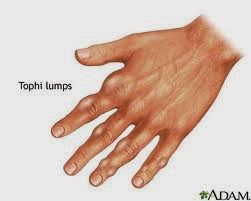

Empat Tanda Telapak Tangan Terserang Asam Urat

Empat Tanda Telapak Tangan Terserang Asam Urat

Tanda Asam Urat Normal Dari Tangan Youtube

Tanda Asam Urat Normal Dari Tangan Youtube